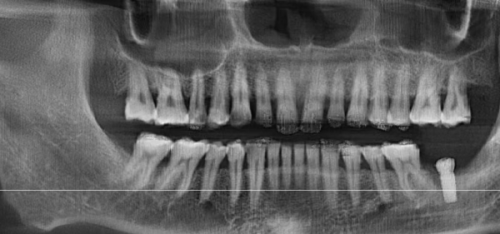

医生的技术水平和种植牙的品牌、质量也是重要因素。经验多的医生在种植过程中能够更精细地操作,提高种植牙的成功几率和使用寿命。而优质的种植牙材料通常具有更好的生物相容性和稳定性,也能为种植牙的长期使用提供保护。